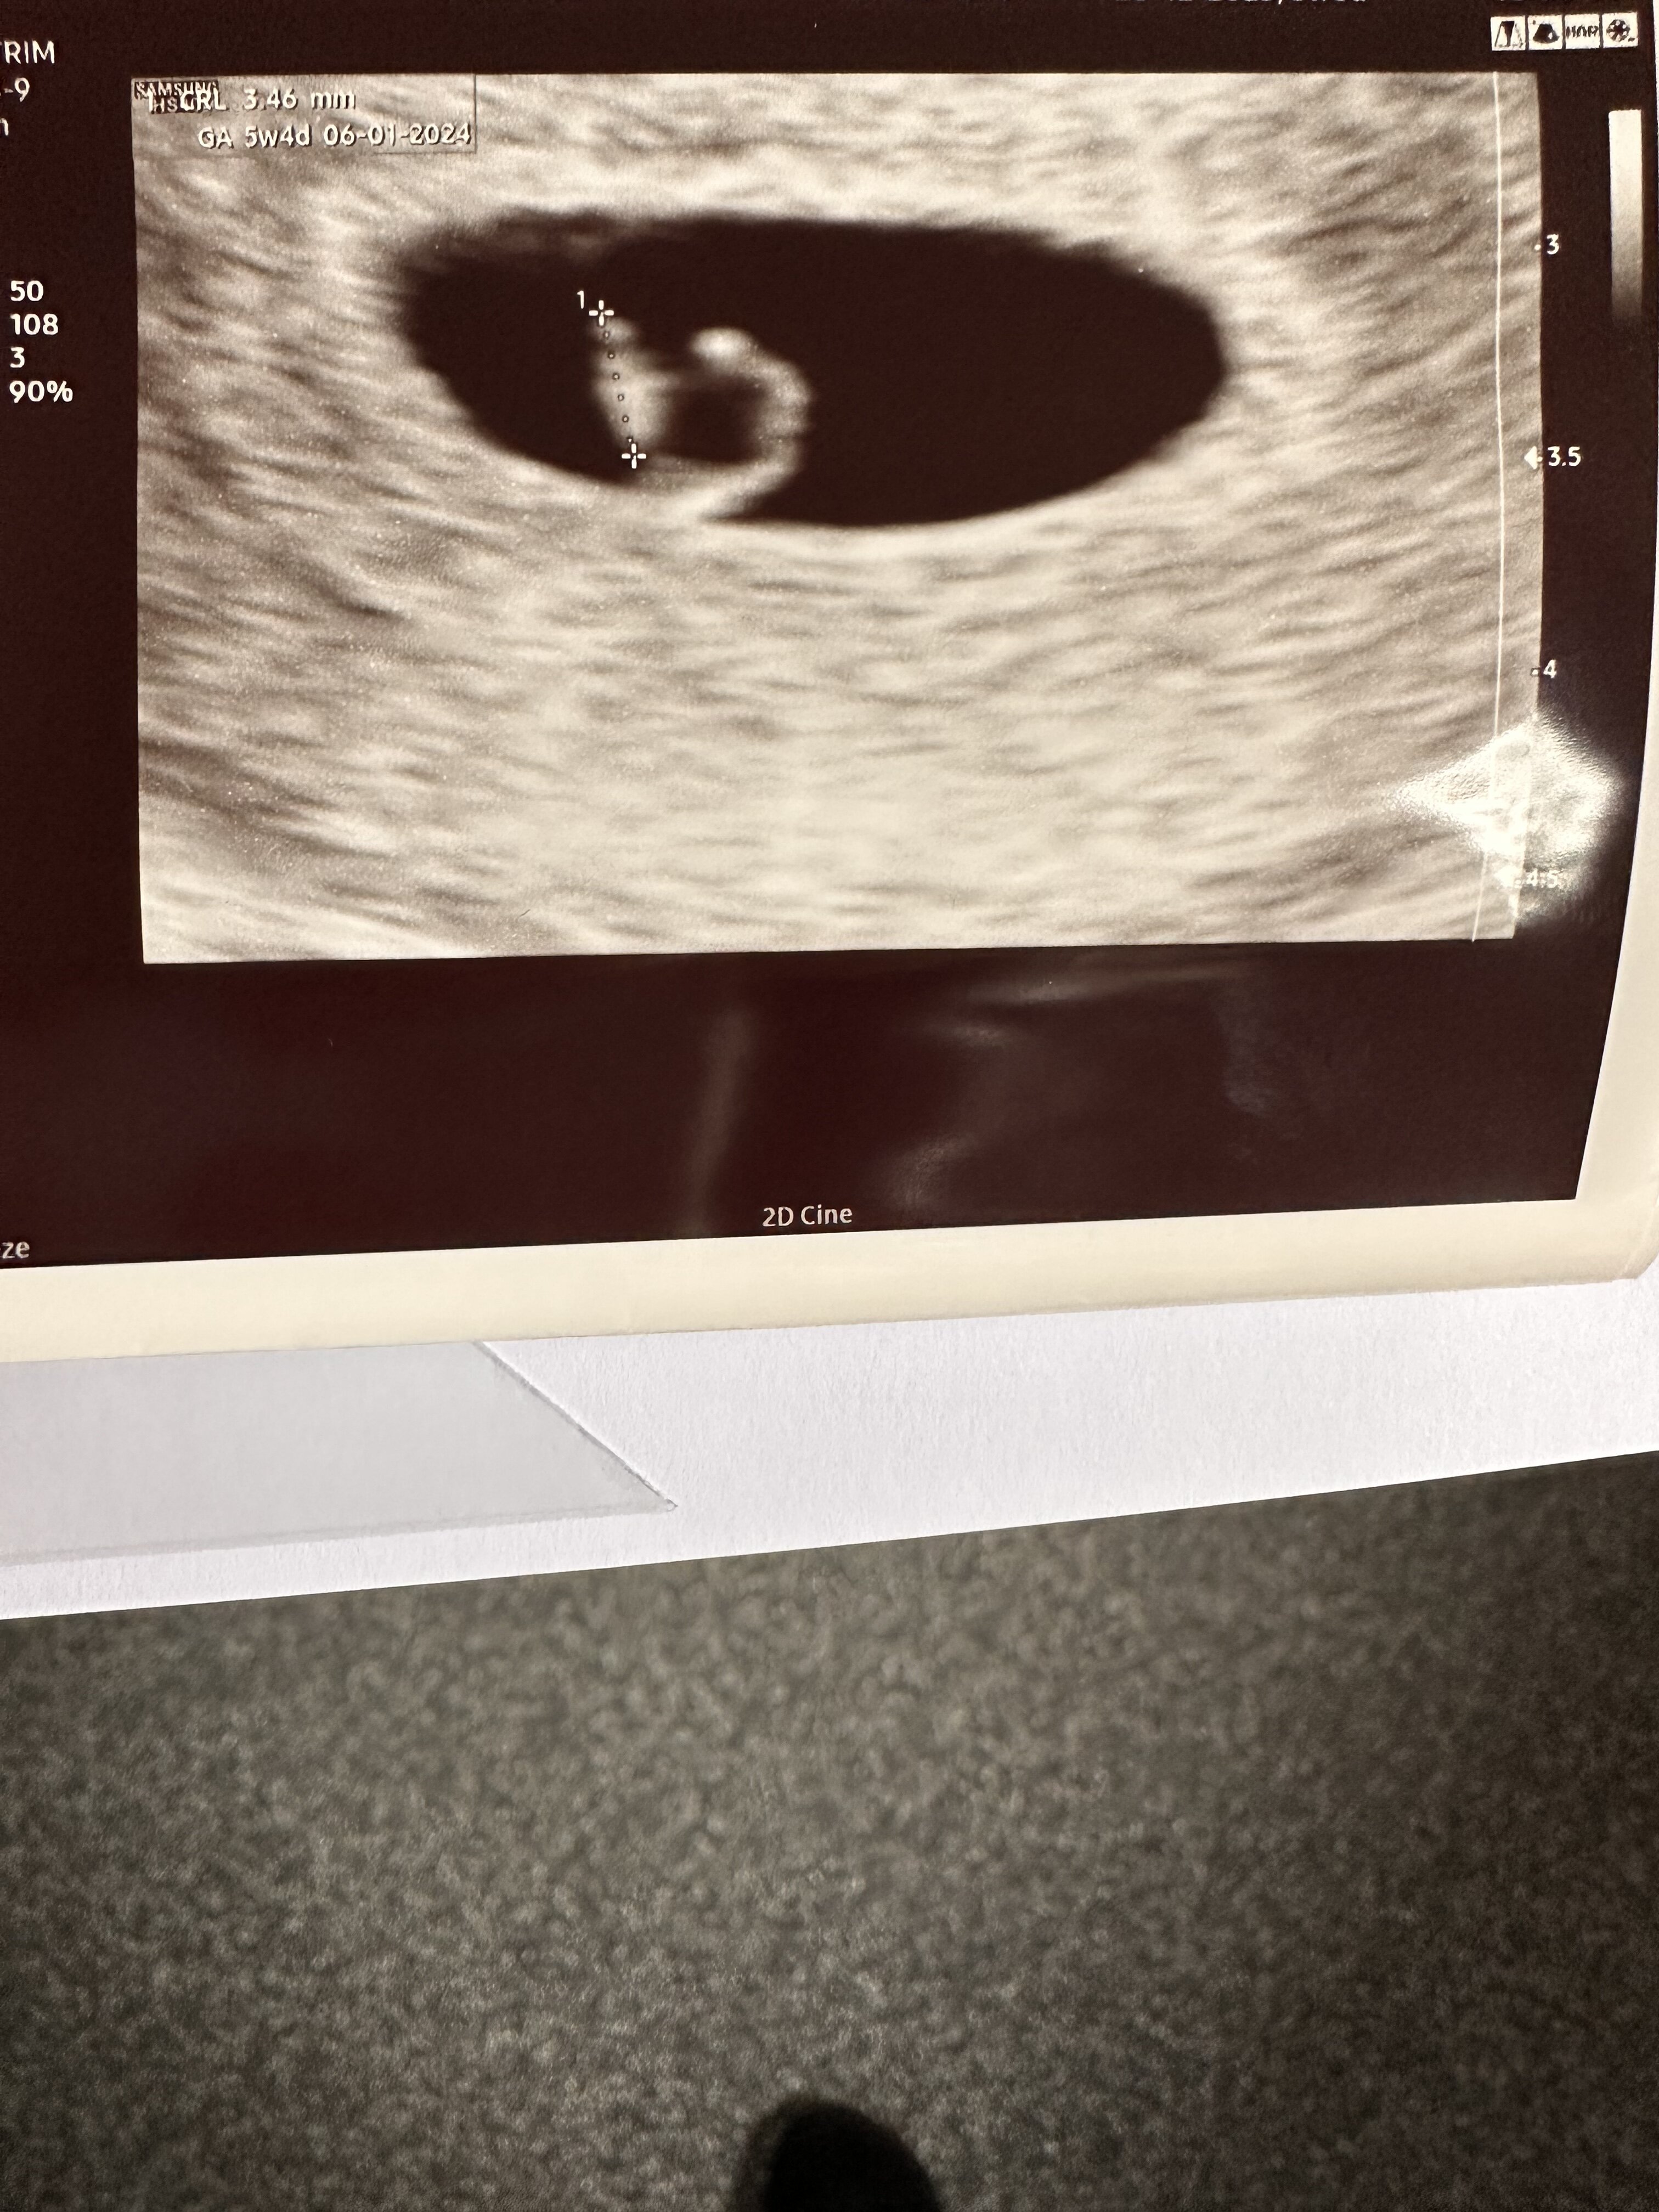

Dzisiaj miałam pierwszą wizytę, na której widziałam bijące serduszko. Według miesiączki 6+6, według wielkości fasolki (3,46mm) 5+4. Termin na 06.01.2024 🥰

• DA877931-7E79-48A9-B0D5-B5B7CC9EA3B3.jpeg

DA877931-7E79-48A9-B0D5-B5B7CC9EA3B3.jpeg

1,4 MB · Wyświetleń: 150